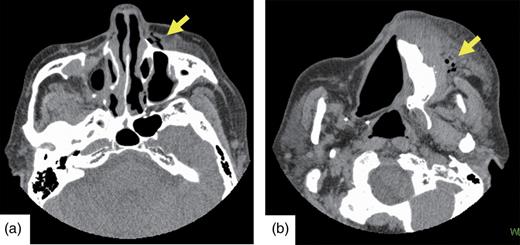

Two hours after the surgery, the patient complained of sudden malar swelling (Fig. 4). Marked swelling was present from the left infraorbital region to the buccal region, and we suspected postoperative bleeding. Thus, we considered hemostasis treatment necessary and reopened the wound under local anesthesia. There were a few hematomas in the wound, but an apparent bleeding point was absent. We removed a hematoma and closed the wound. The CT images revealed that the artificial bone grafted inferior to the membrane had not leaked into the maxillary sinus, and there was no apparent damage of the maxillary sinus membrane. However, the marked malar swelling was associated with air pockets at the alar base and in the angulus oculi medialis region and subcutaneous malar tissue, and no hematoma was evident (Fig. 5a and b). We made a diagnosis of subcutaneous emphysema and administered an intravenous drip containing antibiotics to the patient for 3 days. The swelling improved day by day. We confirmed emphysematous improvement and the graft situation of the artificial bone on the CT images at 12 days postoperatively.

(a and b) Postoperative CT. Emphysema (indicated by arrows) is visible from the left buccal region to the angulus oculi medialis.